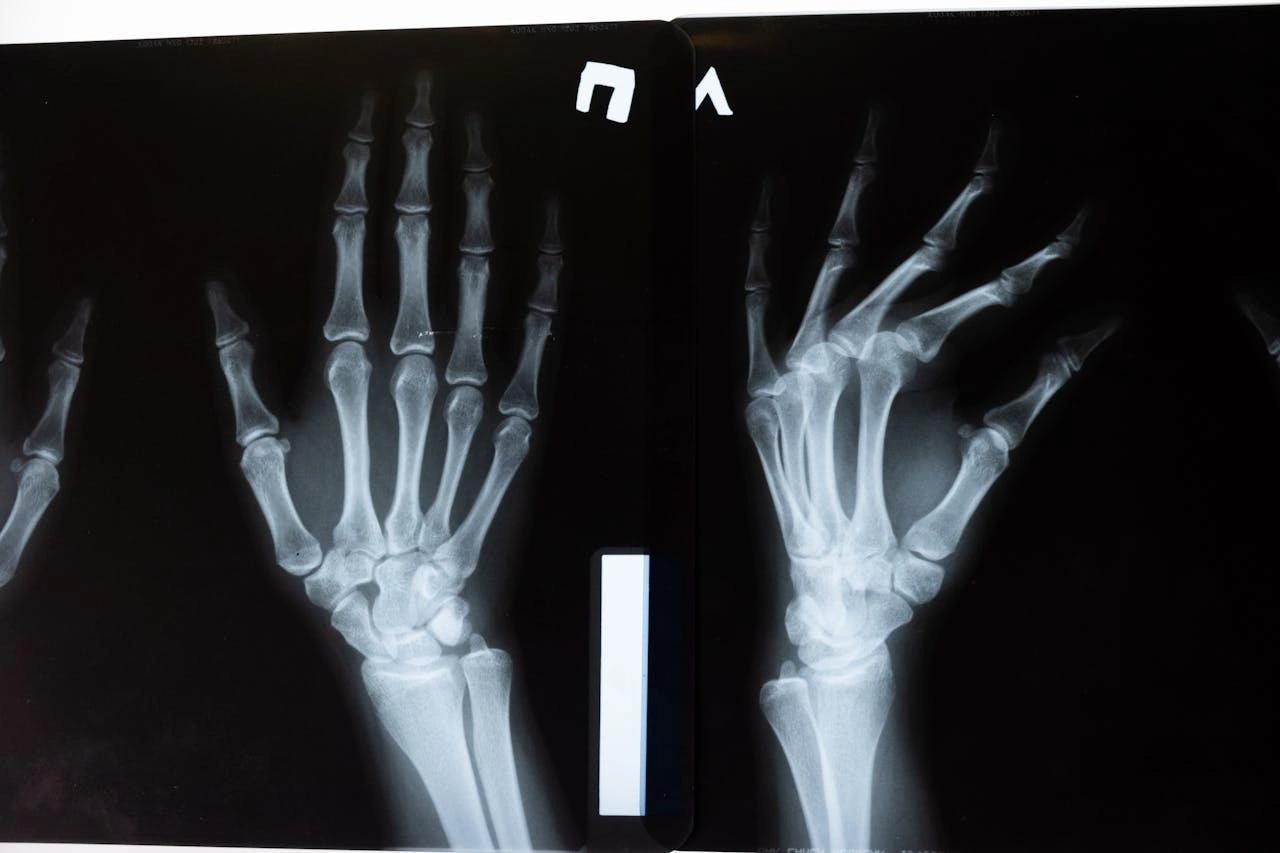

Osteoarthritis: kondisi ini terjadi karena kerusakan tulang rawan pada sendi akibat penuaan atau penggunaan berlebihan. Sendi jari menjadi kaku dan nyeri, terutama di pagi hari.

Rheumatoid arthritis: penyakit autoimun yang menyebabkan peradangan kronis pada sendi, termasuk sendi jari tangan.

Cedera dan trauma: benturan atau jatuh dapat menyebabkan memar, keseleo, atau bahkan patah tulang kecil di sekitar jari.